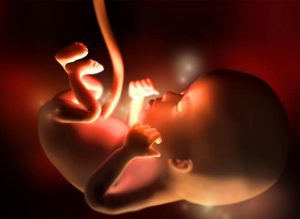

At the 12th week of pregnancy, the last one of the first trimester, your baby’s height can be between 5 and 6 centimeters, and weight between 8 and 14 grams. The heart beats very strong, at 160 beats per minute, and his or her movements begin to increase, though they still remain imperceptible for you.

Your baby’s size is about that of a plum or a passion fruit at this point of gestation. In fact, between the last week and the current one, he or she has grown about 15%. Extremities are already formed, organs begin to mature quickly and even the intestines, connected until now to the base of the umbilical cord, move to the abdominal cavity.

The head, similarly, acquires a rounded shape. The mouth can open and close and the ears are where they belong. The nails begin to form, as do the vocal cords. During the 12th week of pregnancy, the kidneys begin to produce small amounts of urine, and even the first signs of hair appear on the body.

Although sex cannot be determined yet with an ultrasound, the genitalia are in full development at this stage. By this time the baby is also able to yawn, hiccup and swallow. It’s now when the wonders of nature truly start to become apparent to us, as we see the things our developing child is able to do.